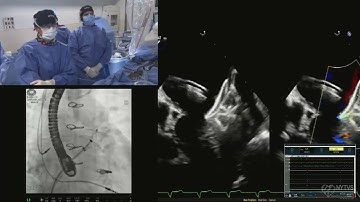

New FEops HEARTguide : LAAO Workflow Amplatzer™ Amulet™ LAA Occluder